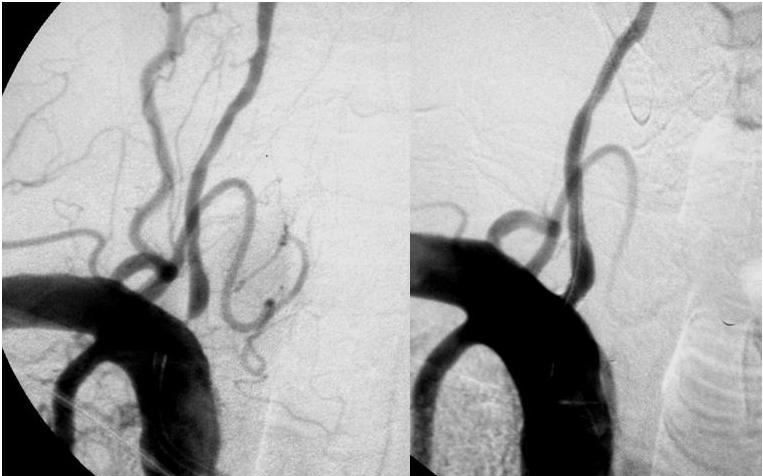

Intervención coronaria percutánea en angina estable, ensayo ORBITA): no es mejor que el placebo

Lancet, 2 de noviembre 2017 En pacientes con angina tratada médicamente y estenosis coronaria severa, la ICP no aumentó el tiempo de ejercicio más que el efecto de un procedimiento de placebo. La eficacia de los procedimientos invasivos se puede evaluar con un control con placebo, como es estándar para la farmacoterapia.